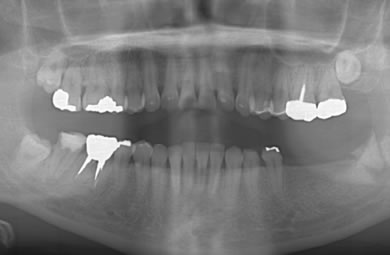

インプラントの症例写真 IMPLANT

インプラント治療+セラミック治療

| 主訴 | 親知らずがかけ、インプラントにした方がいいかどうか知りたく来院した。 | ||||||||||||||||||||||||||||||||

| 治療方針 | 臼歯部の審美的・機能的回復をインプラント治療とセラミック治療にて行う。 | ||||||||||||||||||||||||||||||||

| 治療内容 | インプラント1本、メタルボンドセラミック2本 | ||||||||||||||||||||||||||||||||